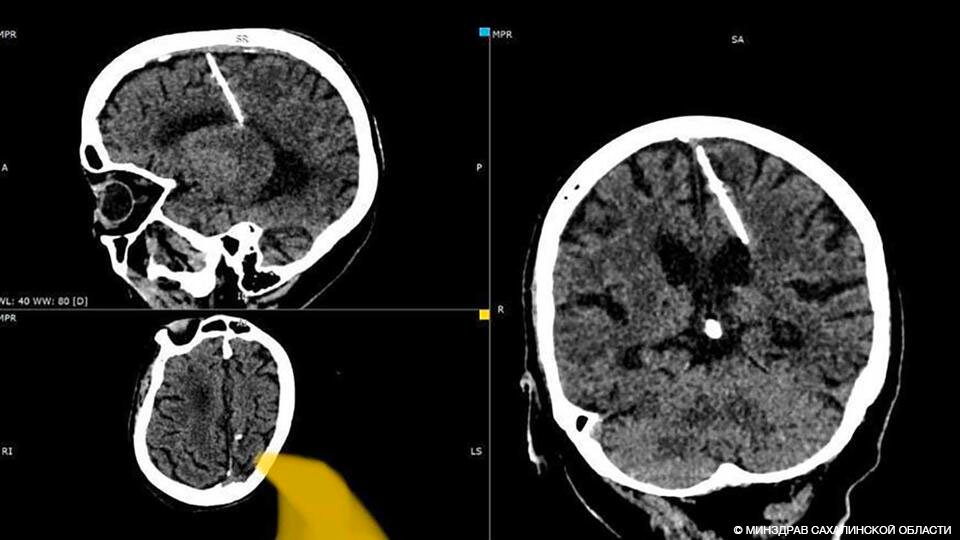

Жительница Сахалина прожила 80 лет с трёхсантиметровой иглой в мозге и не жаловалась на самочувствие. Шокирующую находку на снимке компьютерной томографии обнаружили медики, когда обследовали бабушку совсем по другому поводу.